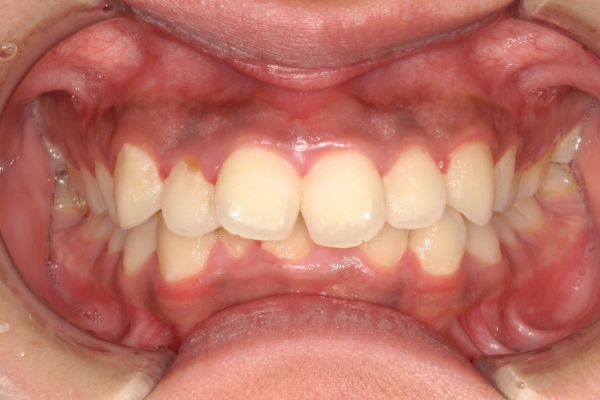

BEFORE

治療前

AFTER

治療後

上顎前歯が1cm近く前方に出ており、叢生を改善しつつ前歯を大きく引っ込めるために上下顎小臼歯の抜歯が必要と診断しました。治療後は、主訴であった前歯の突出と奥歯の噛み合わせのずれが改善され、上下の咬合関係が安定しました。